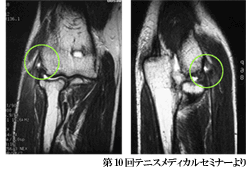

- 右テニス肘 MRI - |

| 腕の運動を支配する神経や血管の元は首にあり、背骨と肩を通して肘に至ります。テニス肘の病態は、背骨の老化現象など加齢変化を基盤として、背骨のバランスの崩れ、肘関節から手指の筋腱の使い過ぎなど、様々な要因が重なって、腕の血液循環と神経の働きが悪くなり、肘関節の疼痛が引き起こされると考えられています。(図1 参照) |